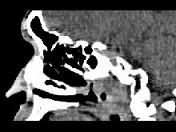

男,52岁,血涕3月余。CT如图所示,最可能的诊断为 ( )A、小唾液腺瘤B、咽旁脓肿C、咽旁混合瘤D、咽部神经纤维瘤E、鼻咽癌

问题 男,52岁,血涕3月余。CT如图所示,最可能的诊断为 ( )

选项 A、小唾液腺瘤 B、咽旁脓肿 C、咽旁混合瘤 D、咽部神经纤维瘤 E、鼻咽癌

答案 E